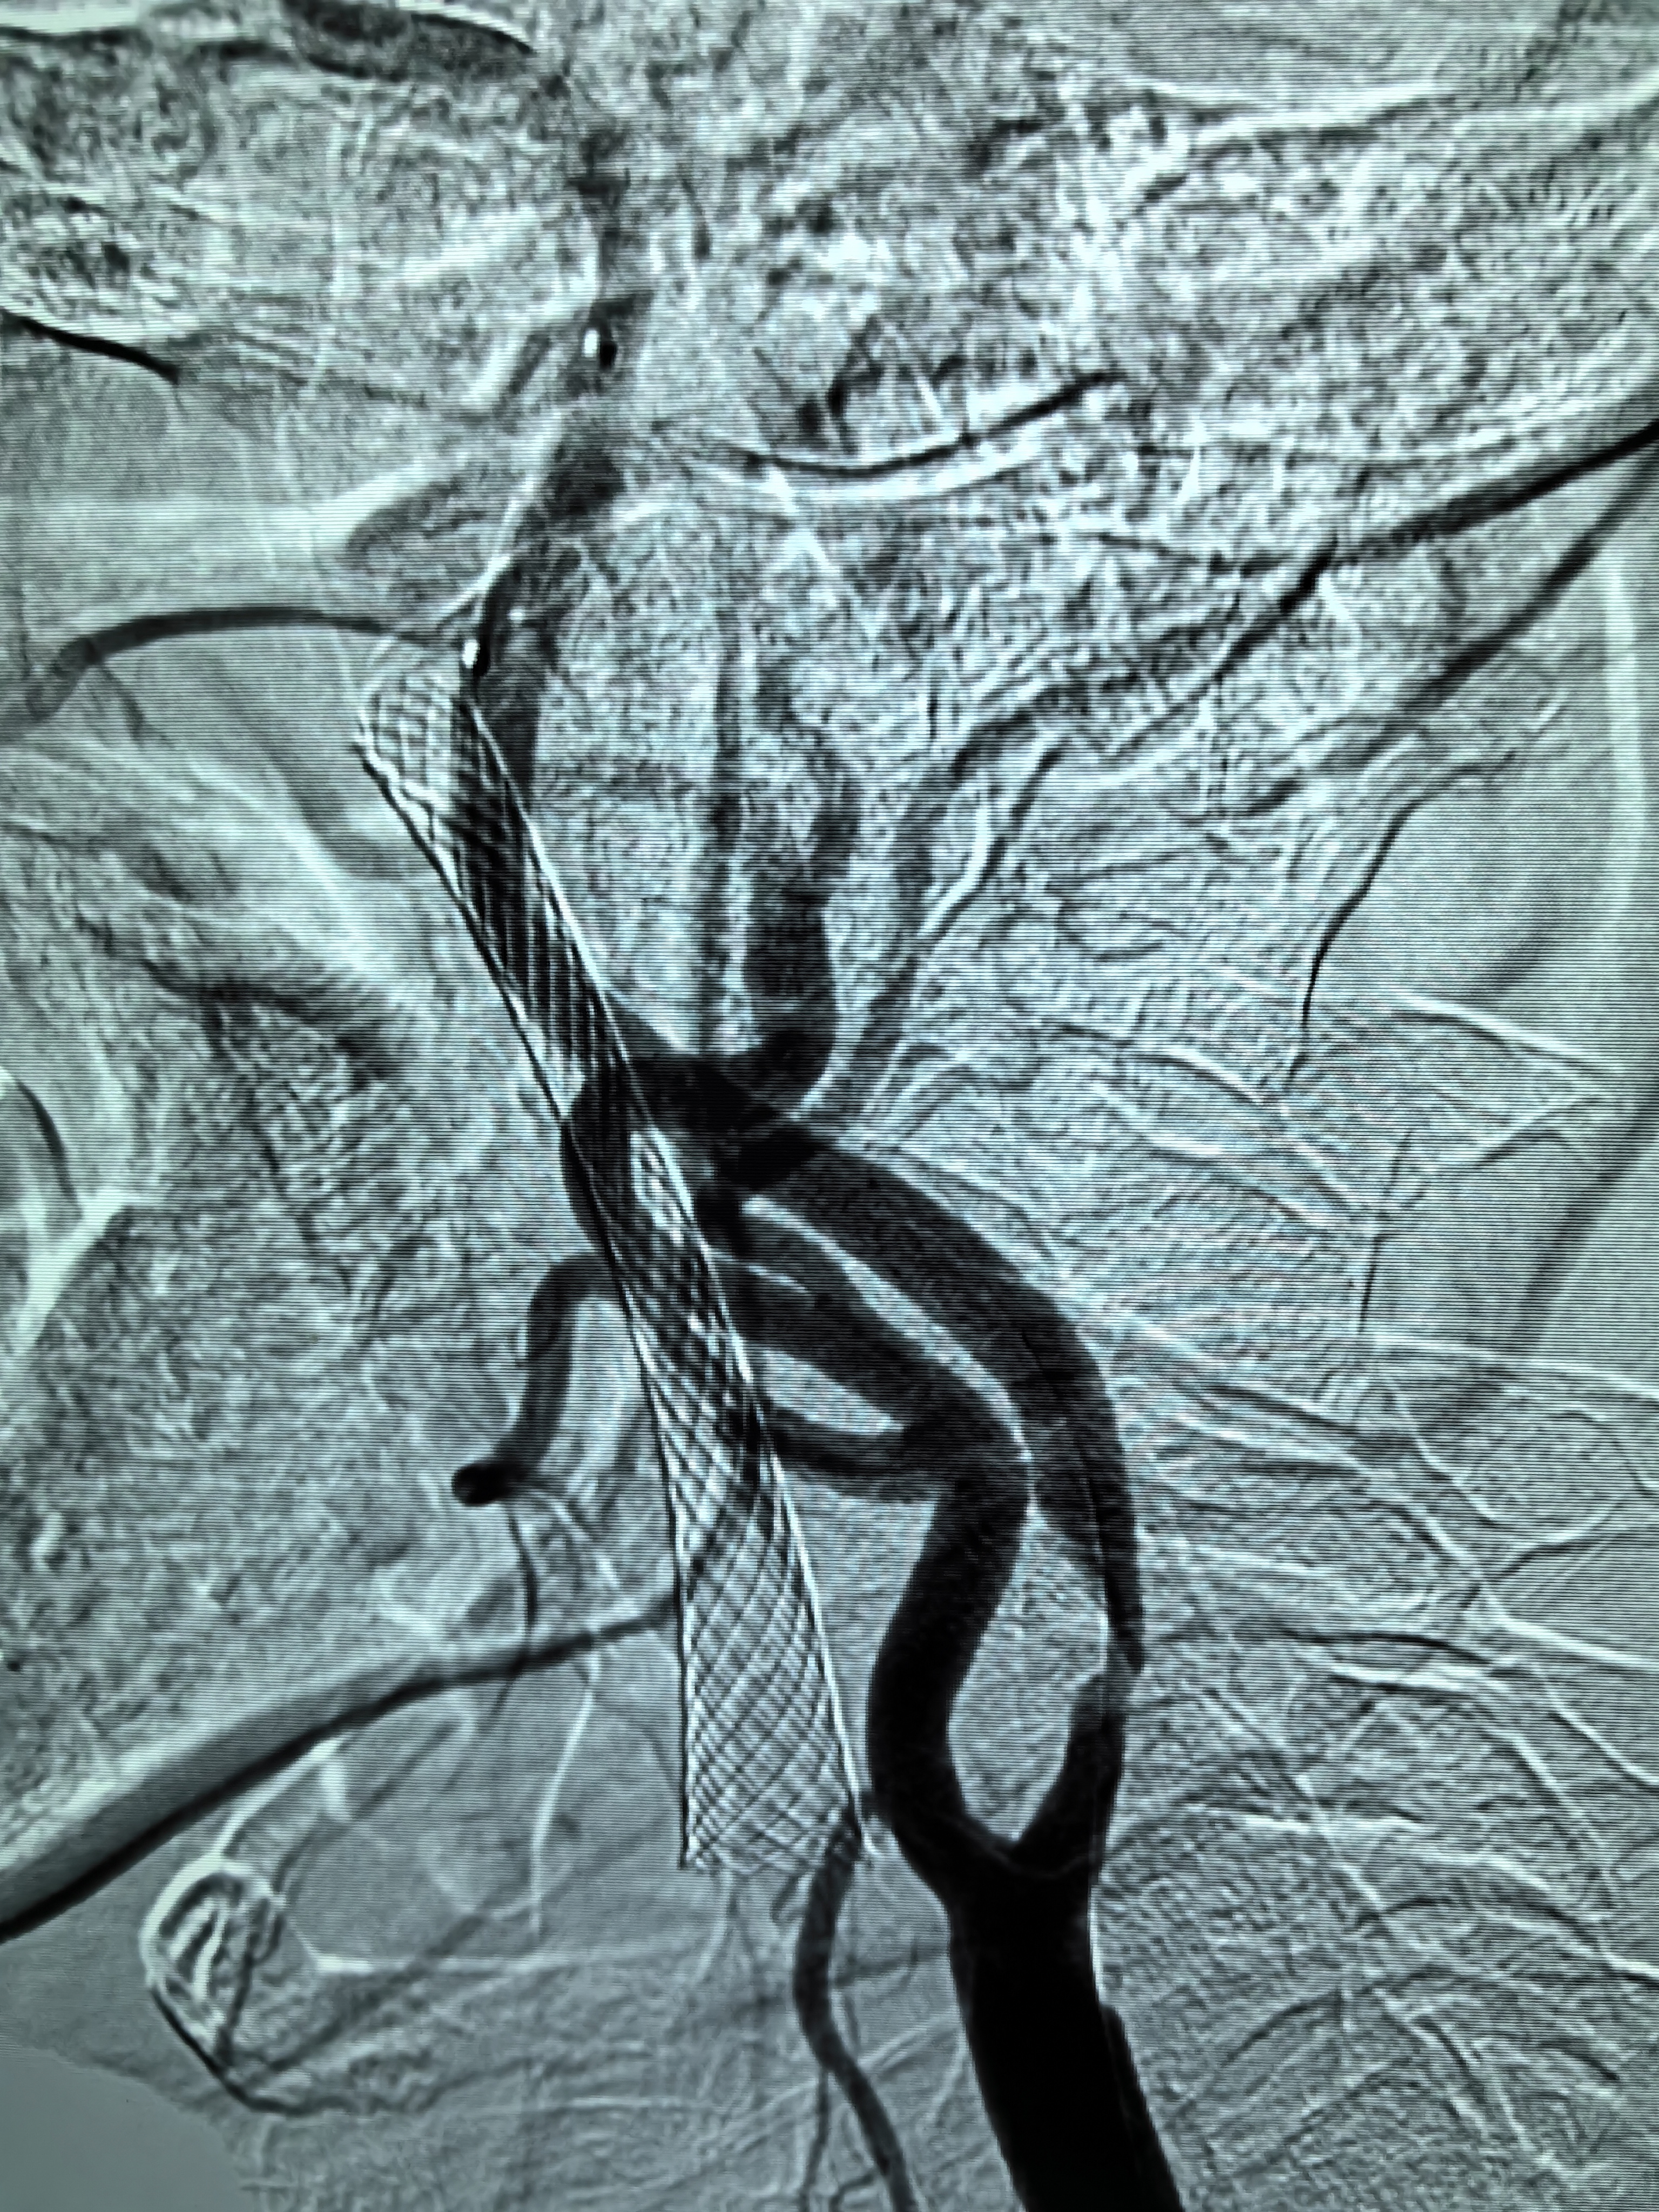

患者男性,70岁,体检发现双侧颈内动脉重度狭窄,1月前行右侧颈内动脉支架成形术,现为治疗左侧颈内动脉狭窄入院。既往高血压病史30年,口服硝苯地平控释片降压,血压控制130/80mmHg。

1、本例患者老年男性,双侧颈内动脉重度狭窄,治疗采取分期处理,间隔4周。

2、左侧颈内动脉从CTA看狭窄合并软斑,具备介入治疗指征。